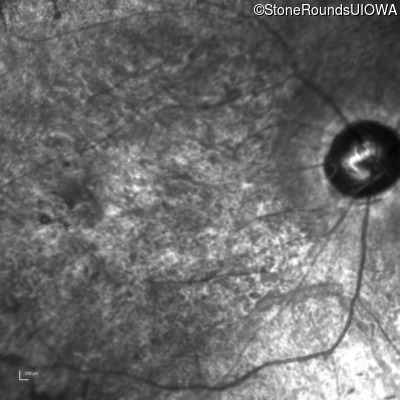

Infrared Fundus Photograph - Right - 20/200 sc

Exemplar